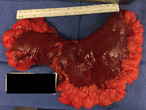

Synchronous malignant phyllodes tumour and invasive lobular carcinoma—case report and review

Henry To and others

Journal of Surgical Case Reports, Volume 2018, Issue 10, October 2018, rjy258, https://doi.org/10.1093/jscr/rjy258